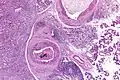

Their histologic appearance is similar to ductal breast carcinoma.

Very high mag.